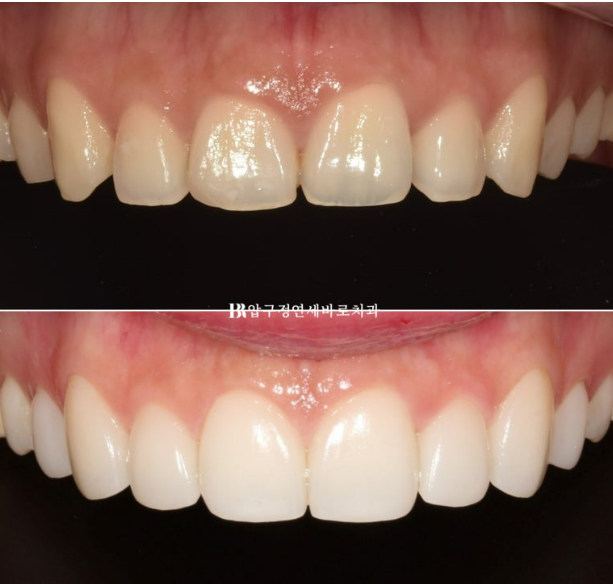

It is noticeable that the two central incisors have been lengthened.

If the two central incisors are made longer and the lengths are made as short as possible toward the canines, the smile line can be changed.

From the existing flat feeling, it can be changed into a beautiful curve parallel to the lower lip.

With just the smile line, it already looks natural and beautiful when smiling, right?

The spaces between the teeth were filled with laminates.

The canines were made to preserve the existing tooth length as much as possible, and from the lateral incisors toward the front teeth, the vertical length was gradually increased,

recreating a smile line with a gentle curved arc downward.

If you look at the front before-and-after photos, the change in the smile line is even clearer.

Shall we draw the smile line?

A natural smile line changes the impression.

A smile line parallel to the lower lip